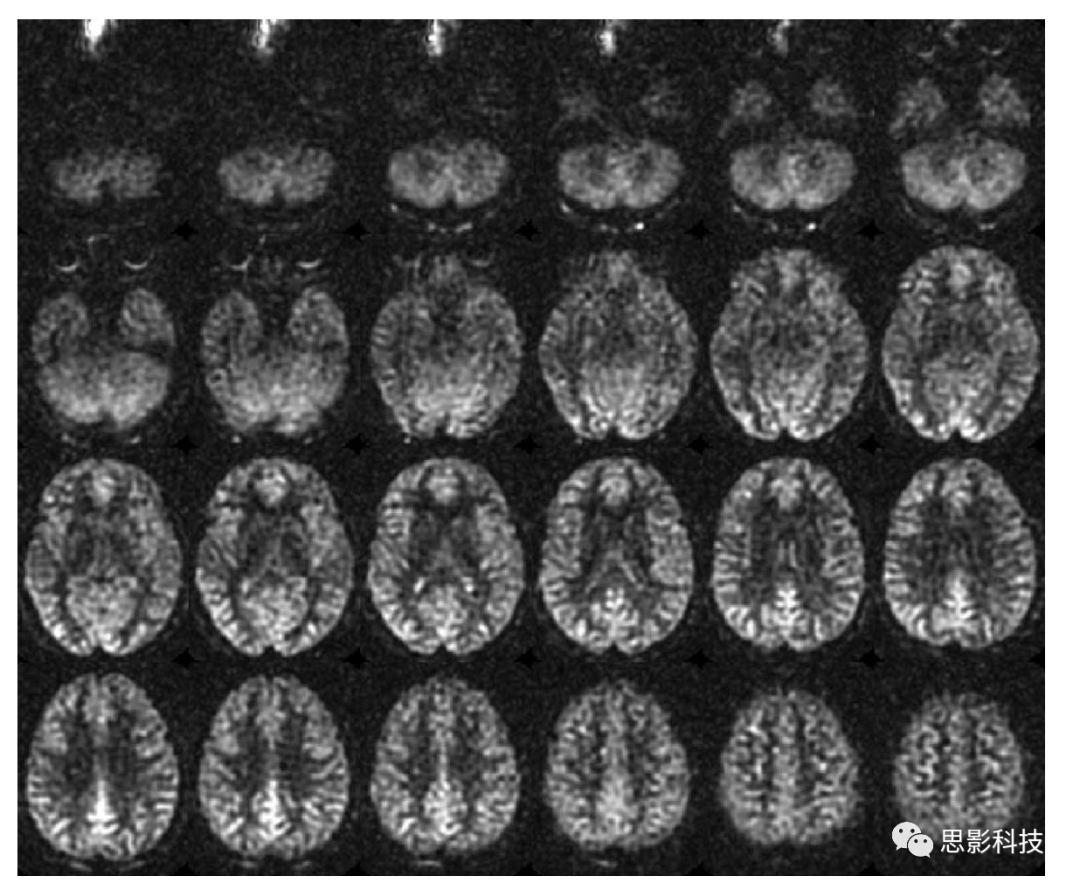

本文的目的在于为已有ASL灌注成像的临床应用提供补充意见,以提高数据的采集质量。ASL技术的发展至今已经20余年。ASL技术采集得到灌注影像质量已达到可用于临床以及研究应用的程度。但是经过多年的发展,有大量的标记方案以及各种模型实现脑血流(cerebral blood flow, CBF)的重建,这使得临床医生以及研究人员难以在各种方案中选择下最优的重建模型。使得构建各个部位的统计以及有意义的临床实验的建立变得复杂,这种广泛而无规范的实验操作减慢了在设备上应用ASL技术的速度,从而限制了该技术的推广。图1即为推荐参数下ASL扫描图像。

Figure 1 正常被试在推荐参数下asl扫描的图像